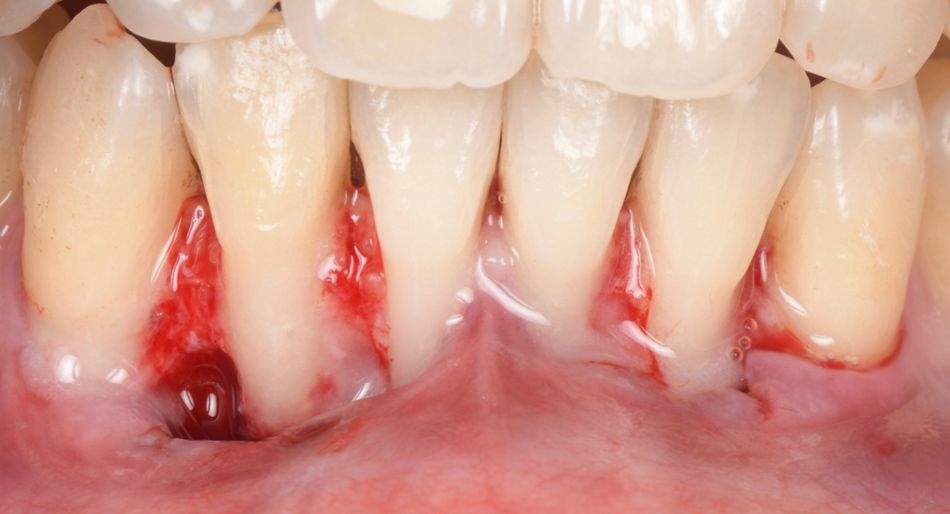

Two split-full-split flaps were raised from teeth #33 to #31 and #41 to #43, with beveled incisions at the base of the papilla (Fig. 3).

Fig. 3